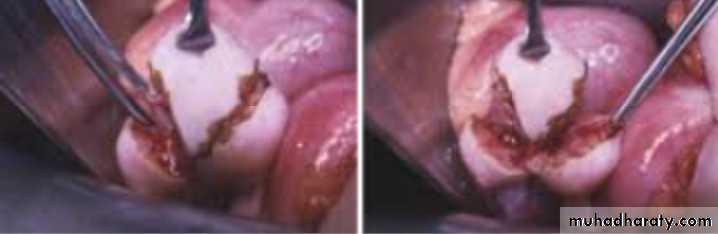

*laparoscopy: PCOS

What is this procedure : wedge resection part of surgical tx in case of PCOS